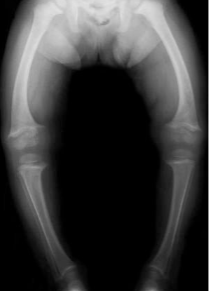

80. 4歲大女孩,自小即便發現呼吸急促合併輕微發紺現象。於左上胸前可聽見一第3度的to-and-fro心雜音。其胸部X光如下。下列何者為最可能之診斷?

(A)B型主動脈弓中斷合併心室中膈缺損 (IAA type B with VSD)。 (B)先天性肺動脈瓣膜缺乏症(congenital absence of pulmonary valve)。 (C)總肺靜脈回流異常(Total anomalous pulmonary venous connection)。 (D)大血管轉位合併心室中膈缺損及肺動脈狹窄(TGA with VSD, PS)。 (E)主動脈狹窄合併逆流(aortic stenosis and regurgitation)。